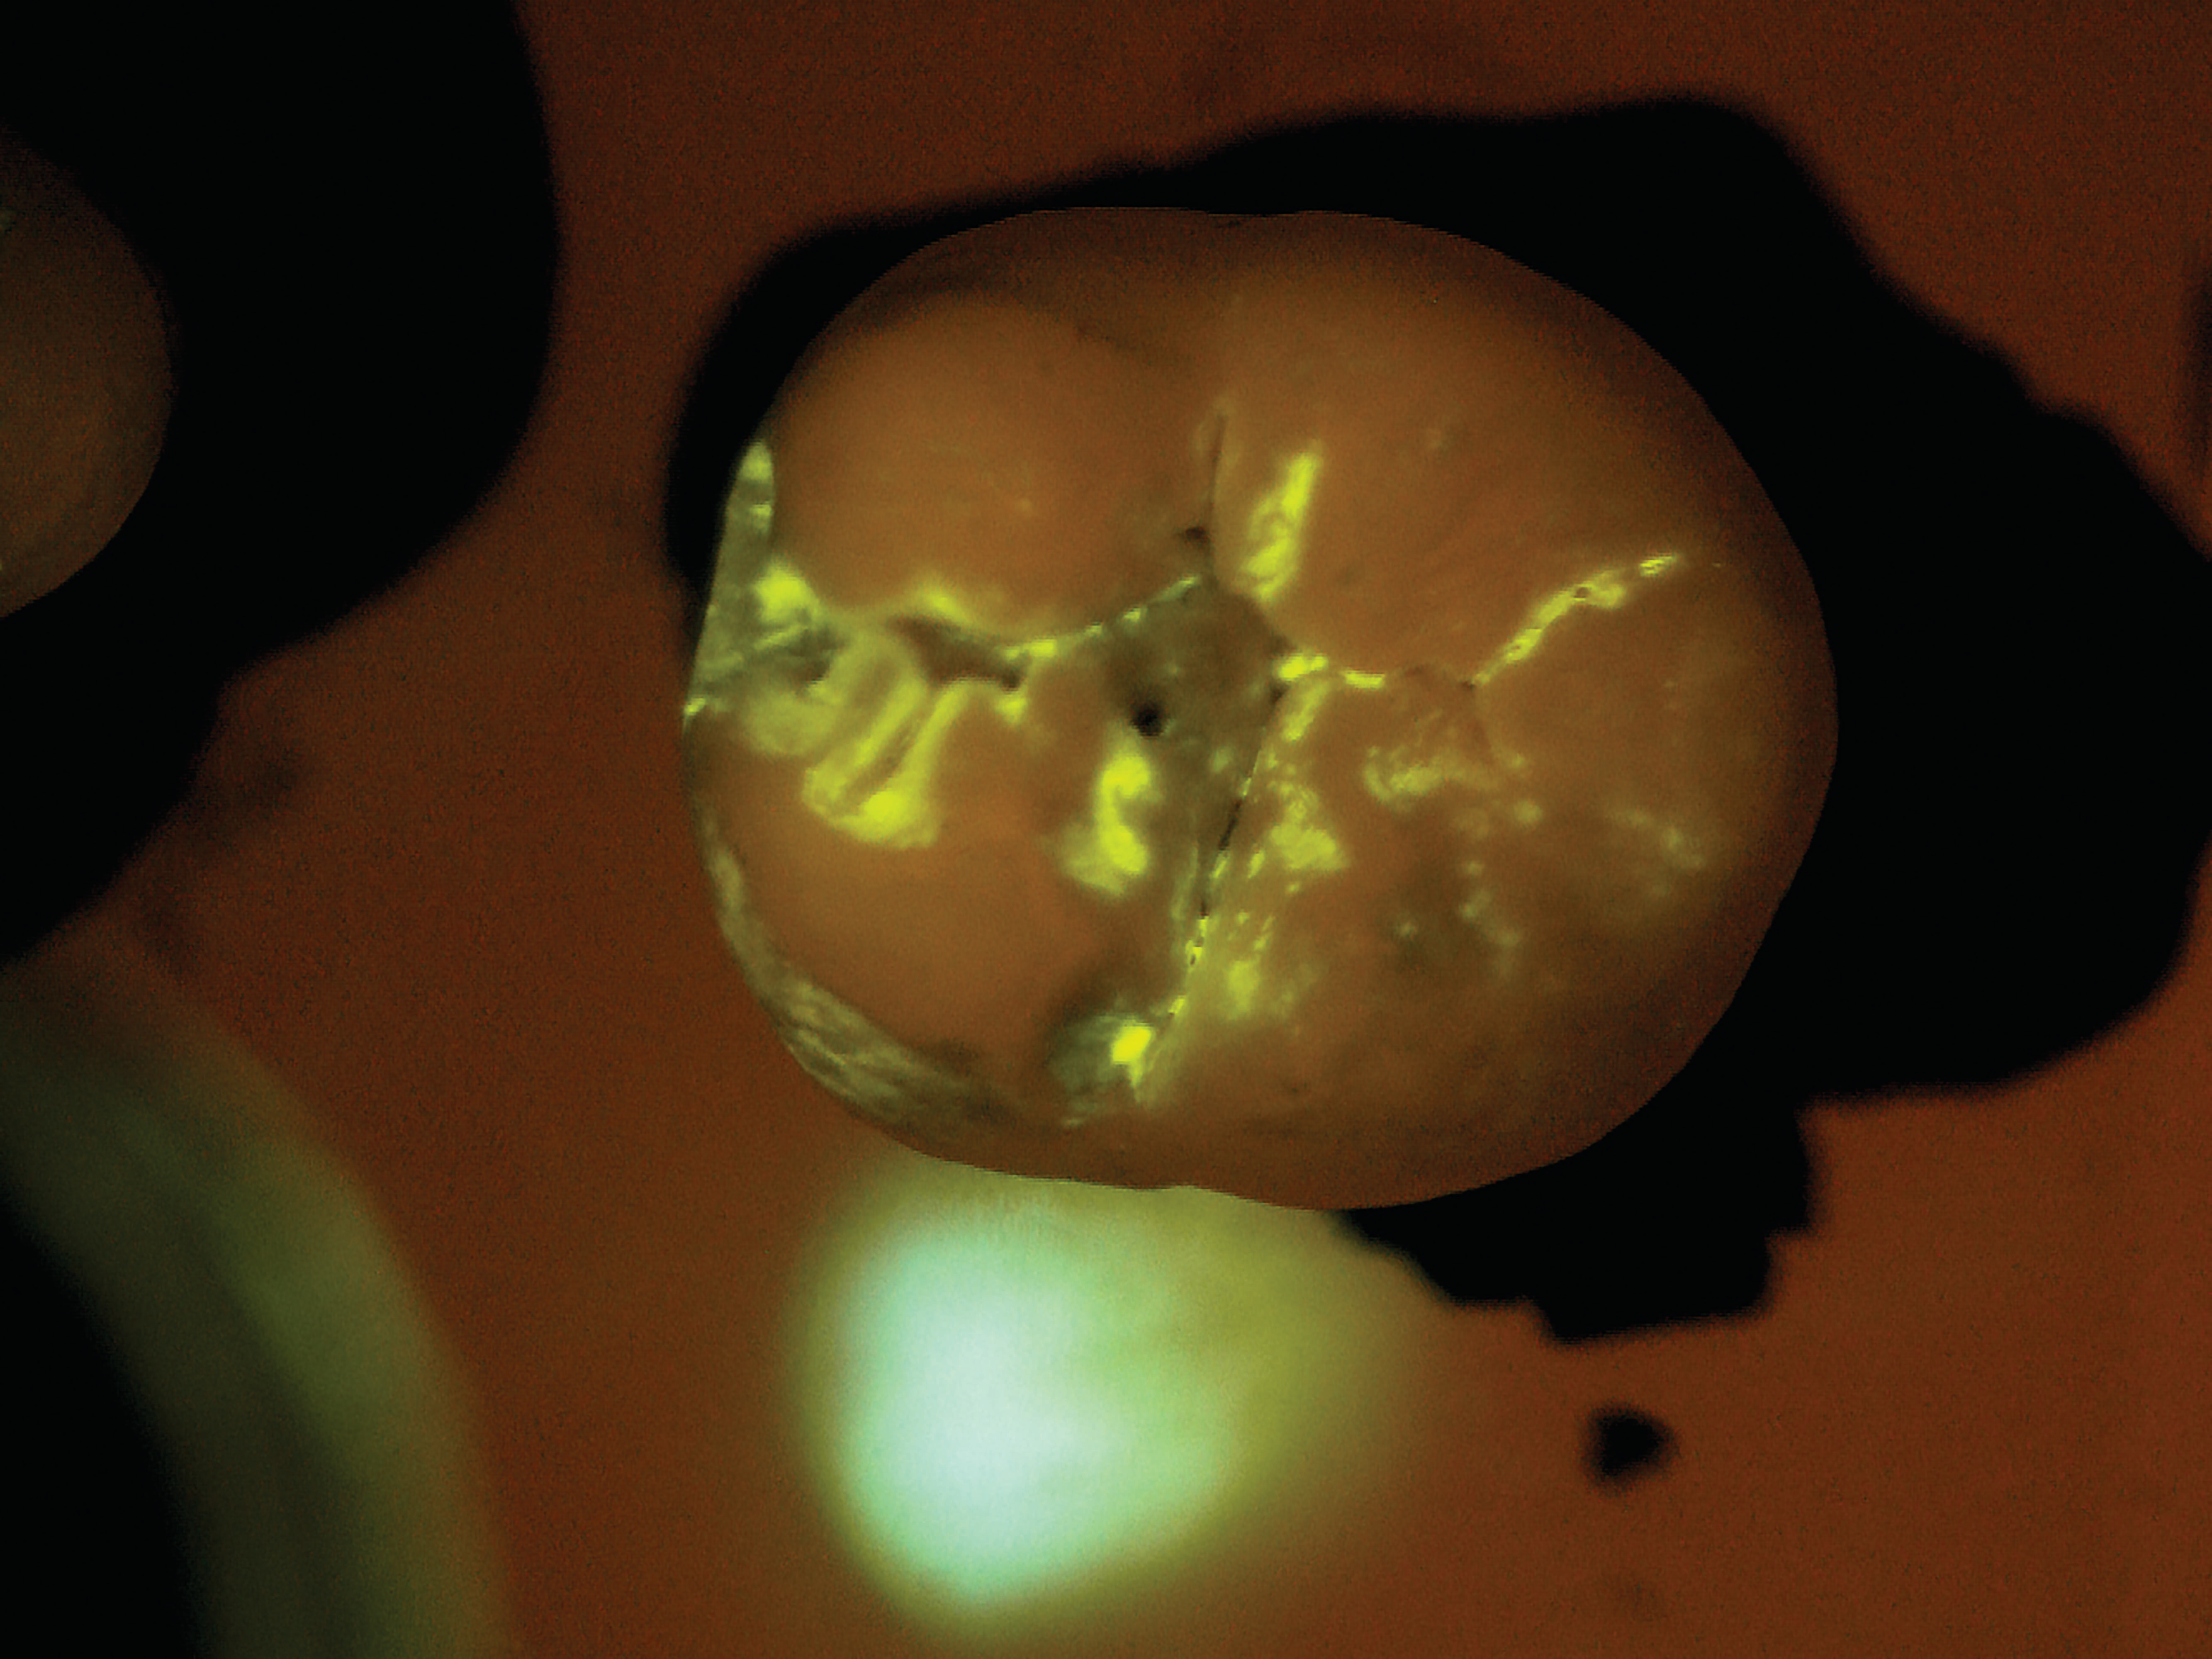

SB: The practice would administer the diagnostic test as part of a routine prophy exam. We have developed a mouth rinse where the targeted starch particles are dispersed at a low concentration in water. The patient rinses first with the diagnostic solution and then with plain water. All that remains after the water rinse are the particles that have penetrated

the tiny porosities in the enamel and attached themselves temporarily to the active subsurface lesions. The particles contain molecules that fluoresce or light up under exposure from a standard blue curing light. Within seconds, the dentist receives a direct visual diagnosis because the illuminated areas indicate areas of porosity.

After the patient drinks the mouth rinse containing the targeted starch particles and then rinses with water, particles adhering to enamel porosities fluoresce under a standard blue curing light.